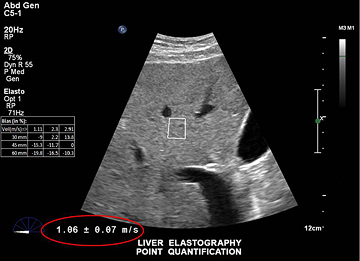

Durch überraschend einfache und schnelle Messungen der Lebersteifigkeit trägt die Philips Scherwellen-Elastographie zur leichteren Beurteilung von Lebererkrankungen bei.

Mit der Scherwellen-Elastographie von Philips lässt sich die Lebersteifigkeit auch bei schwer schallbaren Patienten überraschend schnell und einfach messen. Dieses nichtinvasive, anwenderfreundliche Verfahren erfordert nur einen schnellen Handgriff für Sonografiker und ist für Patienten nahezu schmerzlos.

Die Philips Elastographie erzeugt Scherwellen in der Leber mittels Schallkraft durch einen fokussierten Ultraschallstrahl. Das System überwacht die Ausbreitung der Scherwellen, misst ihre Geschwindigkeit und zeigt sie dann in einem leicht zu befundenden Format an.

Durch einen einfachen, nichtinvasiven Scan wird die Lebersteifigkeit in Sekundenschnelle gemessen.